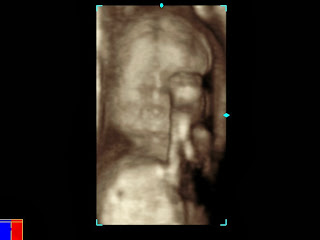

Some of the 3d images are just so awesome! It looks like a real baby, if you know what I mean! A few days after the scan we heard back from the doctor's office that everything looks right on track and that they got all of the images that they needed.